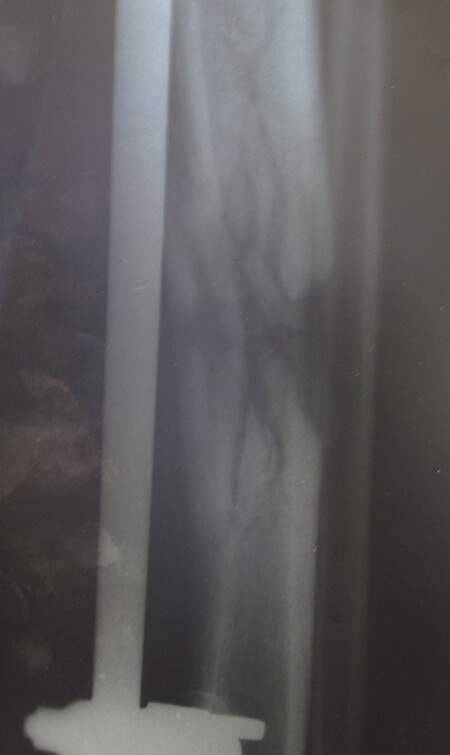

2a: 19-year-old male with a Gustilo IIIb middle 1/3rd tibia and fibular fracture, left leg

2b: Treated acutely with debridement and external fixator: x-ray at 2.5 months shows good alignment and signs of union.

2c: Fracture site was covered by a local fasciocutaneous flap within 11 days of the acute injury

Figure 2a-c: Success story of patient treated by local surgeons: orthoplastic collaboration in country.